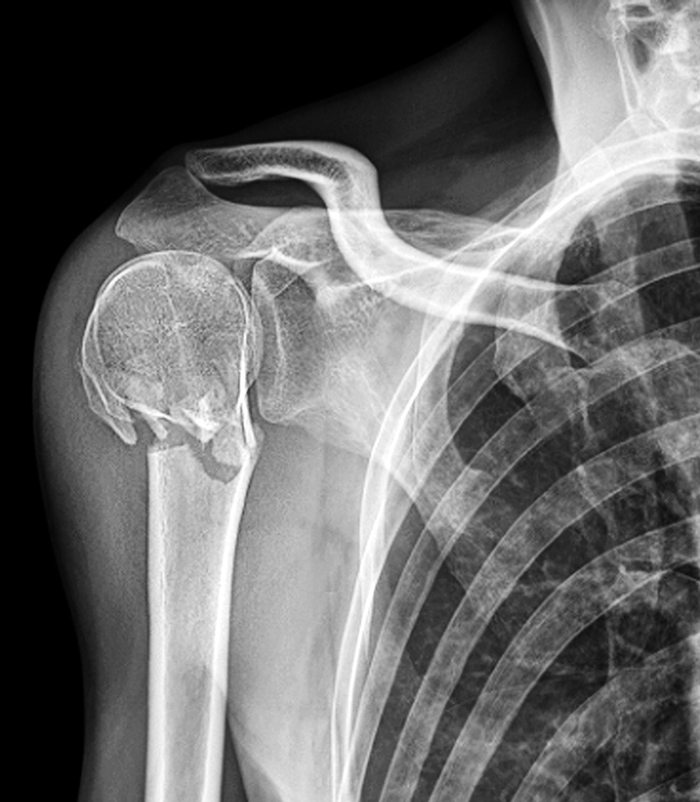

Författarna sammanfattar sina fynd med att de inte kunde påvisa några skillnader i utfall mellan operativ och icke-operativ behandling av dislokerad proximal humerusfraktur hos vuxna. Foto: Science Photo Library/IBL

Författarna sammanfattar sina fynd med att de inte kunde påvisa några skillnader i utfall mellan operativ och icke-operativ behandling av dislokerad proximal humerusfraktur hos vuxna, och att fynden inte stödjer den utveckling som i dag ses; att allt fler opereras för denna typ av fraktur.